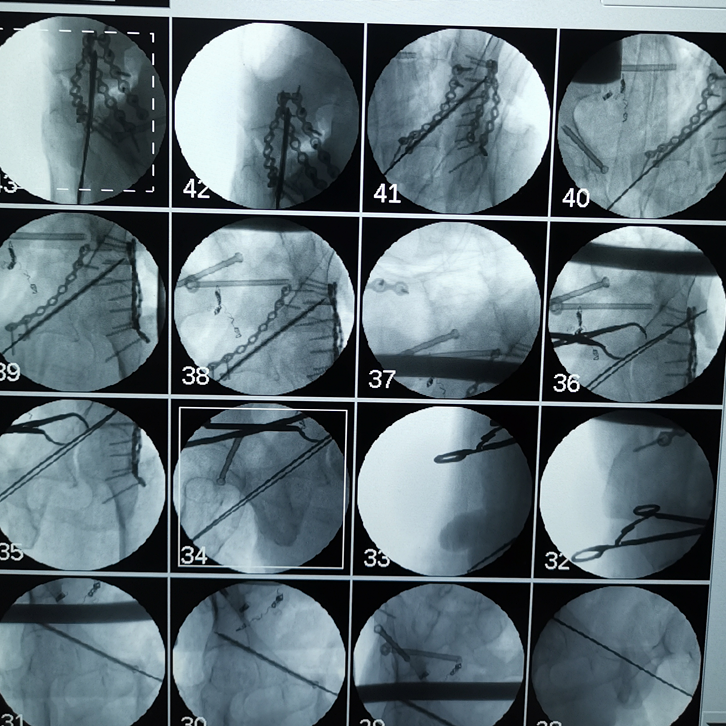

吸痰、冰毯、抗炎、抗凝、氣管切開、下腔靜脈濾器植入……見招拆招,ICU的日日夜夜,在嚴(yán)重創(chuàng)傷并發(fā)癥的狂風(fēng)暴雨中,創(chuàng)傷中心與ICU醫(yī)護(hù)人員的精心照料,為韓大叔撐起了生命之傘。周春峰與周袁平主任節(jié)假無休,除夕前,還為韓大叔做了雙側(cè)骨盆髖臼骨折確定性手術(shù)(雙側(cè)前后路切開復(fù)位內(nèi)固定VSD引流術(shù))。

雙側(cè)骨盆髖臼骨折前后路手術(shù)